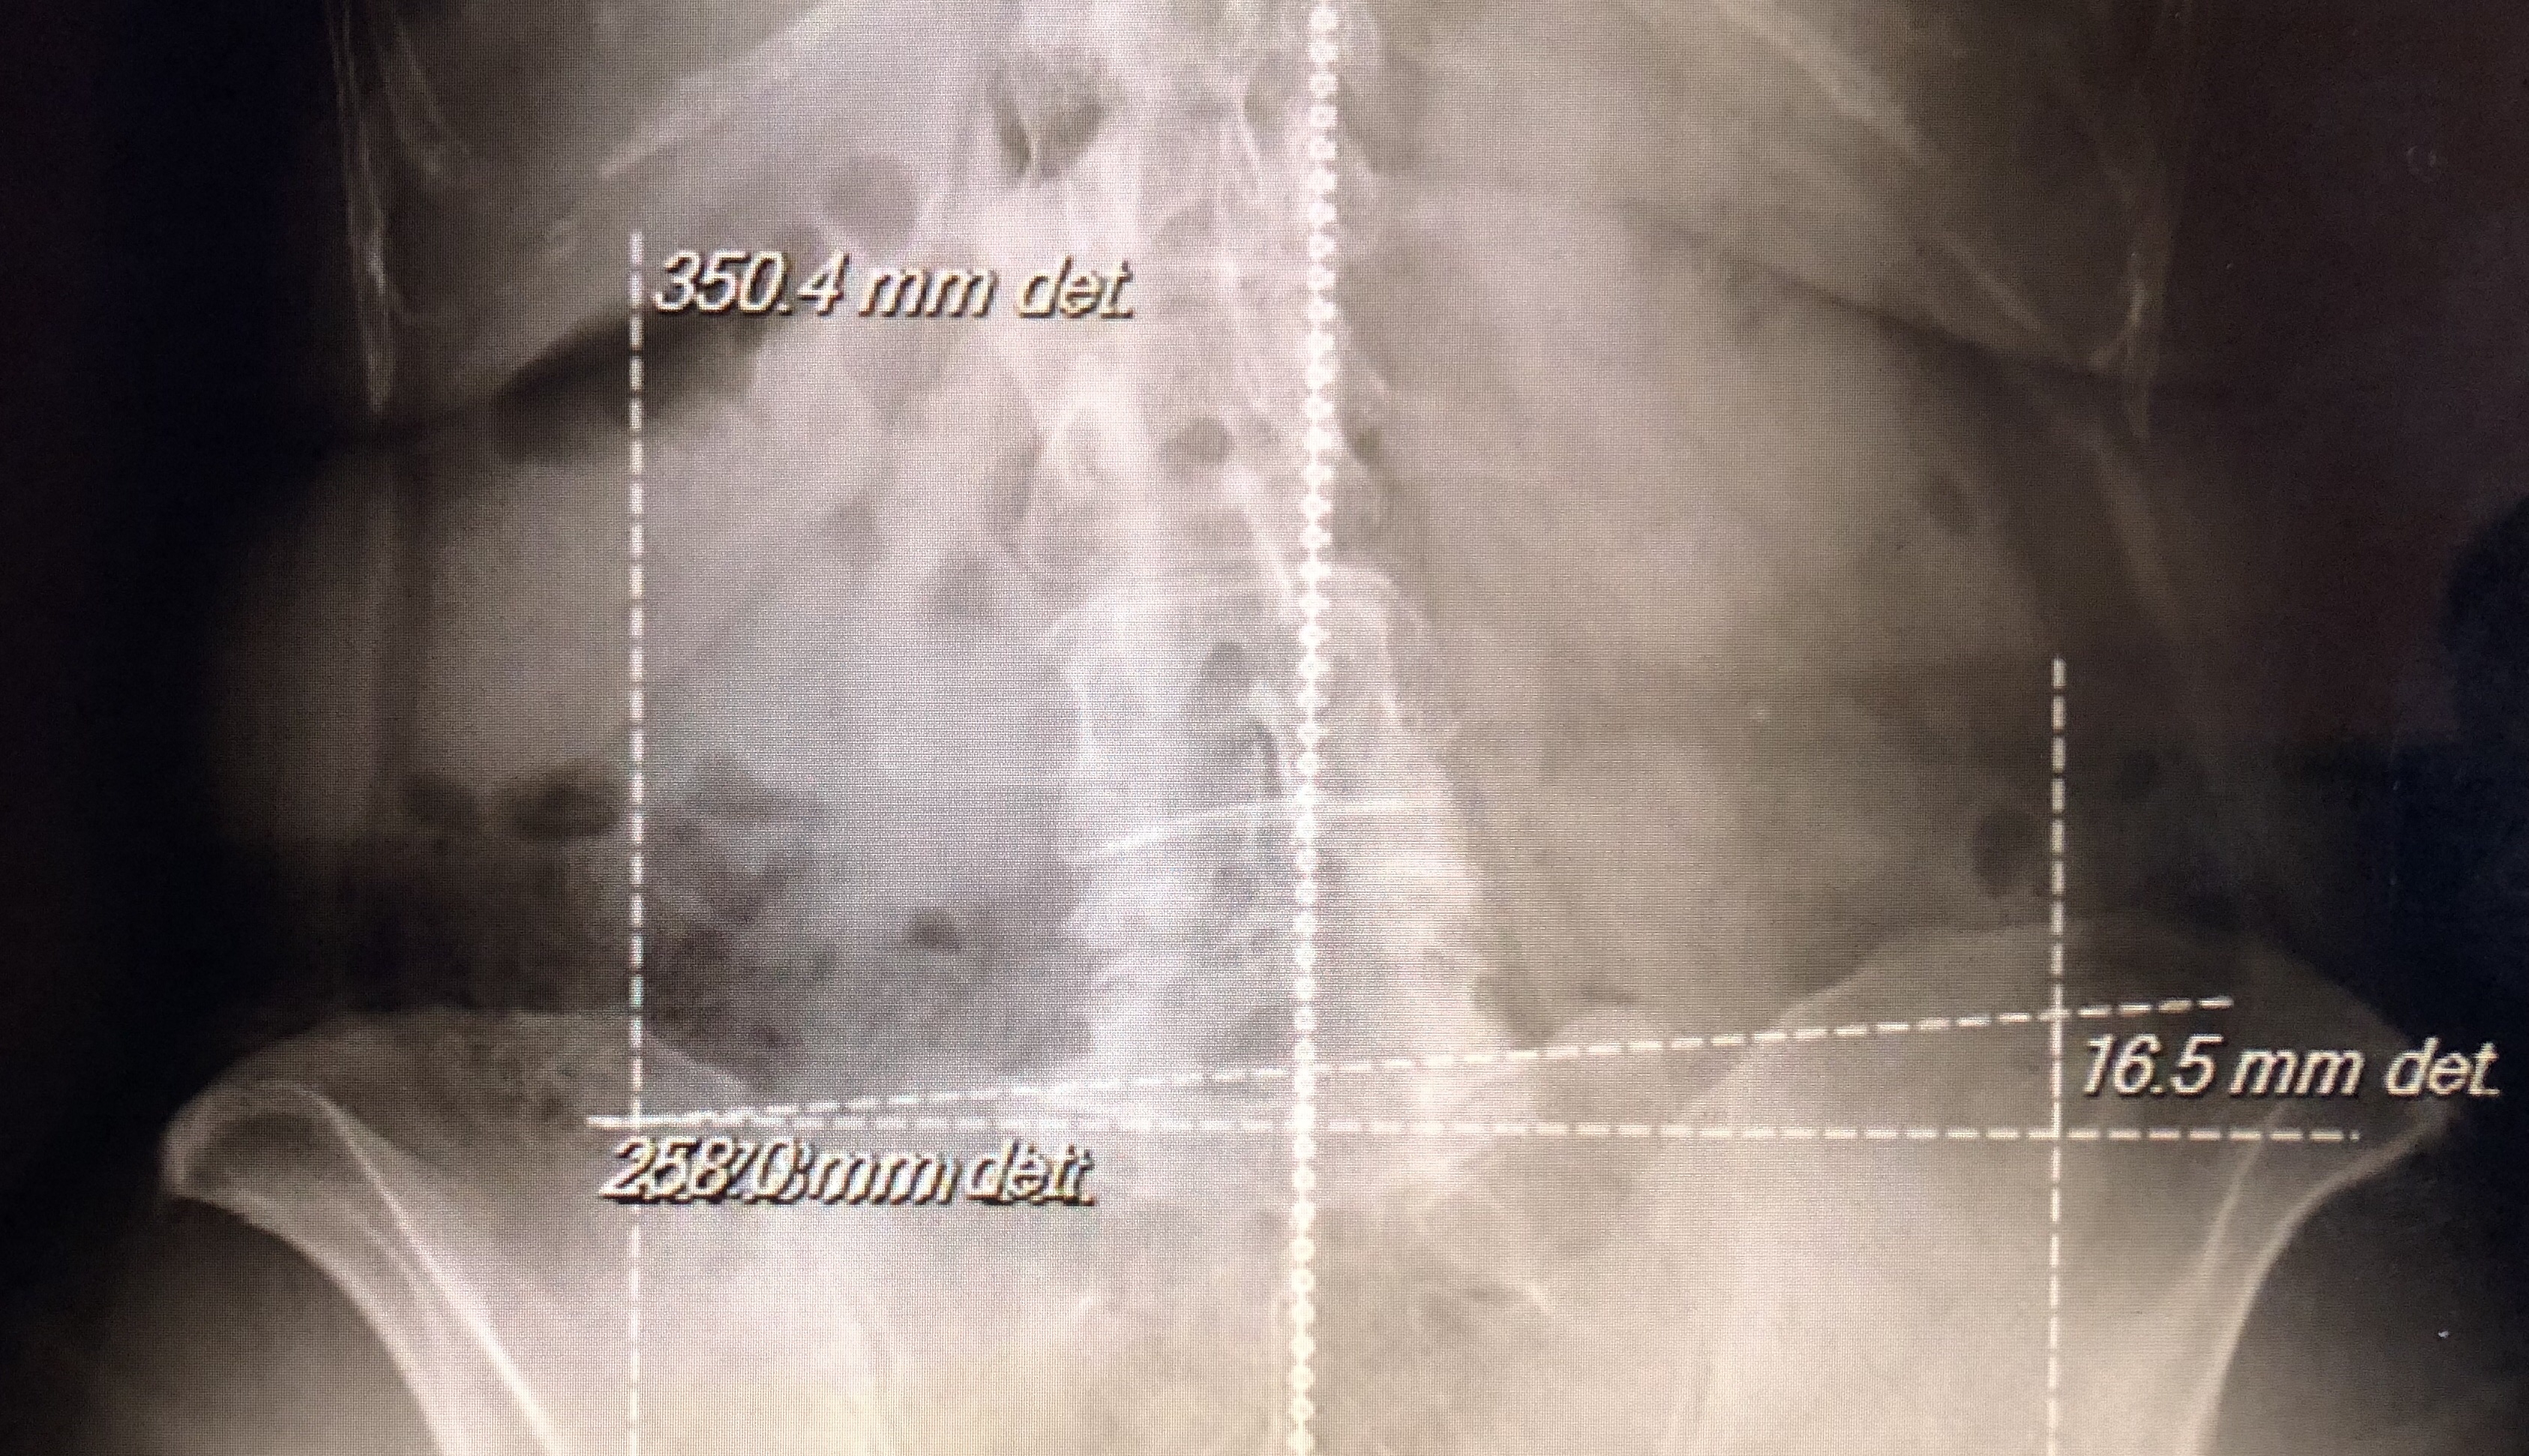

Three weeks ago I had an appointment with a neurosurgeon regarding my back. We discussed the possible treatment for my herniated disc. I have had surgery previously in 2001 and 2005, so I wasn’t looking forward to a third surgery. For the first time I was told that my body could heal on it’s own given time. I left there with some hope, and a follow up in three weeks.

At my three week follow up, we decided surgery was my best option.